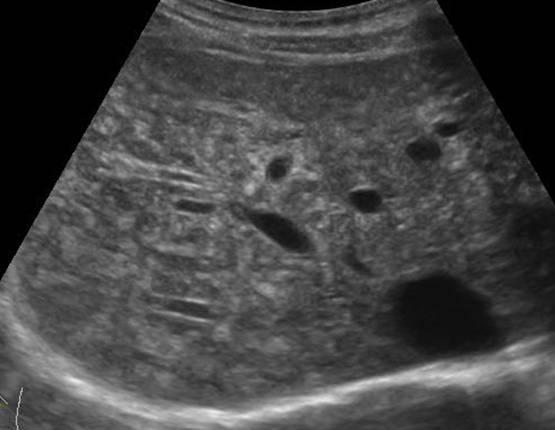

Hamartoma đường mật

» Thông tin: Nam giới – 34 tuổi.

» Lâm sàng: Kiểm tra sức khỏe.